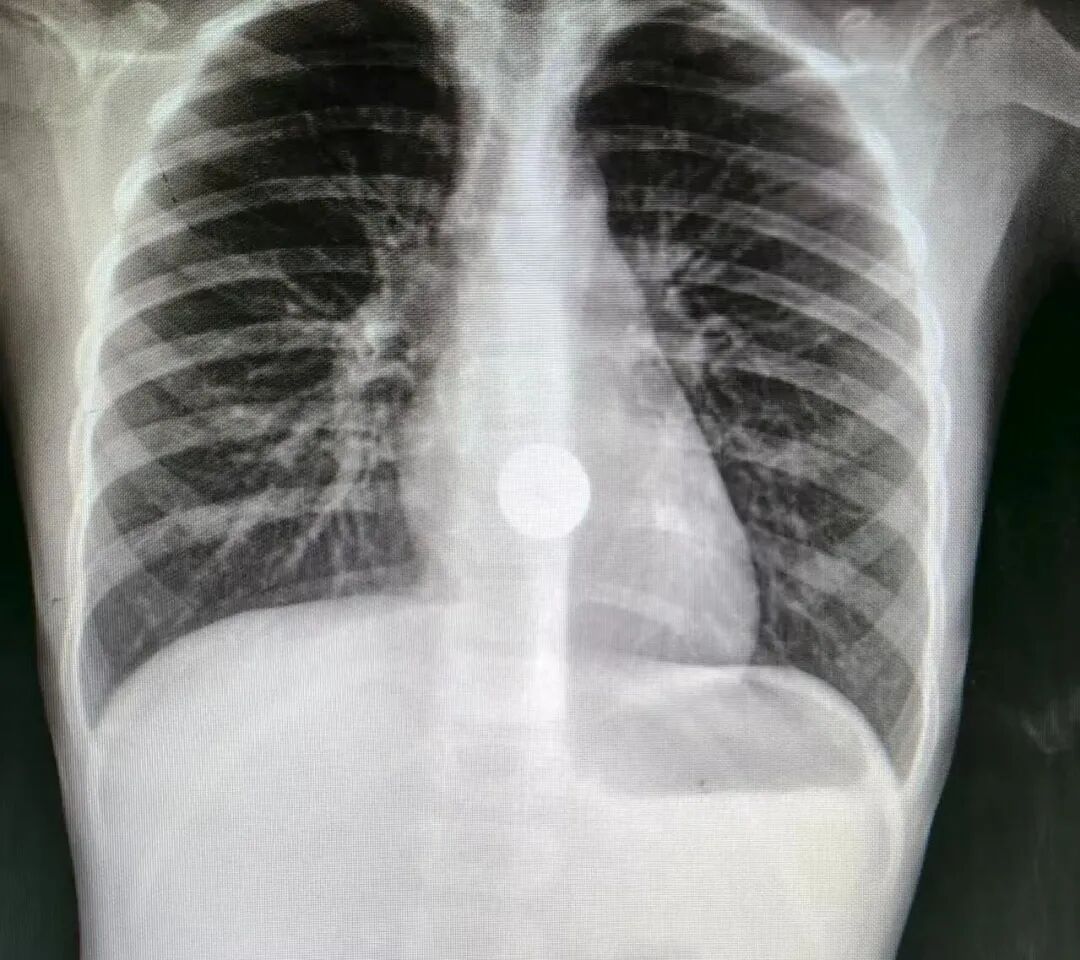

惊险!6岁女童硬币卡喉,医生20分钟内镜取出化险为夷